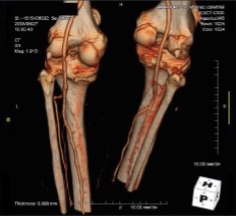

The arterial supply to the peripheral tissues e.g. legs and feet are the most common to be affected by disease and can lead to disabling symptoms. Our CT peripheral angiogram provides exquisitely detailed images of the peripheral arteries to detect narrowing or obstruction to blood flow, with the result and images being reported by a renowned expert in this field.